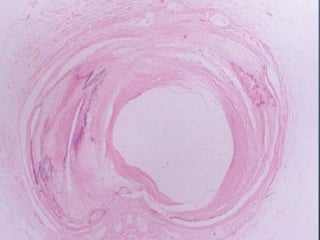

Vasculares:

•Desgarro trasversal de la túnica intima (signo de

Amussat).

•Desgarro de la adventicia (Signo de Etienne lesser).

•Desgarro en las venas yugulares el desgarro de la

túnica (signo de Ziemke).

SIGNOS INTERNOS Cuello: Traumatismosvasculares, musculares, óseos, laríngeos, neurológicos y digestivos. Vasculares: •Desgarro trasversal de la túnica intima (signo de Amussat). •Desgarro de la adventicia (Signo de Etienne lesser). •Desgarro en las venas yugulares el desgarro de la túnica (signo de Ziemke).